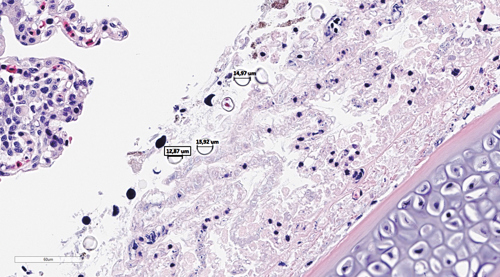

Perlesnormanet (Link: Artikkel i Norsk Veterinær Tidsskrift) har gitt høy dødelighet i de fleste regioner høsten 2023. Eksponering for perlesnormanet kan være en av årsakene til den økte forekomsten av karskader vi registrerer i høstmånedene. En god sykehistorie er derfor nødvendig for å kunne gi en mer nøyaktig årsakssammenheng og diagnose. Av alle innsendelser senhøsten 2023 der vi så gjelleforandringer som kunne relateres til eksponering for irriterende materiale i vannet, herunder maneter, var perlesnormanet oppgitt i sykehistorien i ca 45% av sakene. Hovedfunnene i disse sakene var milde til moderate lamellære karskader. I de sakene med mest alvorlige vevsskader så vi områder i gjellene med akutt til subakutt vevsdød (nekroser) av lameller og filament. Sammen med disse skadene så vi i enkelte gjeller tilsynelatende tomme runde strukturer med diameter på ca 13-15 μm og distinkt, refraktil kapsel. Vi tolker disse strukturene til å være nematocyster, det vil si giftkapsler perlesnormaneter bruker til å skade eller drepe fiender og byttedyr.

Bilde: Bildet viser vevssnitt fra gjeller fra laks i sjø etter angrep av perlesnormanet. Det ses runde strukturer med en diameter på ca 13-15 μm, tolket som nematocyster (målestrek), assosiert med nekroser (vevsdød) av gjellevevet.